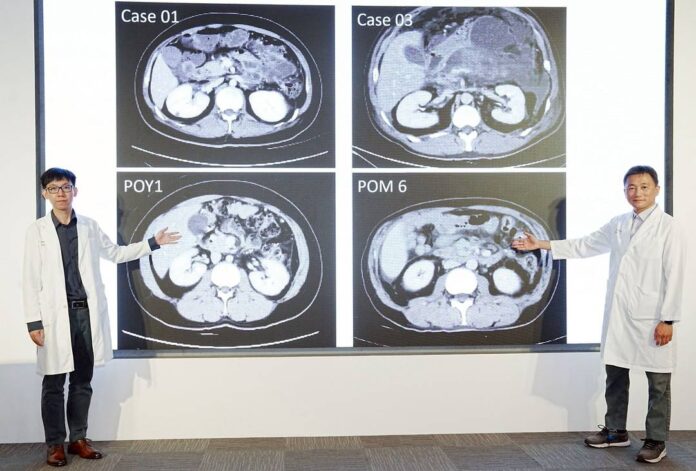

該醫院胰臟醫療團隊在葉俊杰醫師帶領下,去年收治包含許先生等7名重症壞死性胰臟炎病人,病因包含膽結石、酗酒及高三酸甘油脂,平均年齡約52歲,皆屬感染性壞死高風險個案。經一般外科、消化內科與放射診療科多專科團隊採取階段治療後,其中5名病人已順利康復出院,另2名病人持續追蹤治療中,整體存活率較傳統治療有所提升。